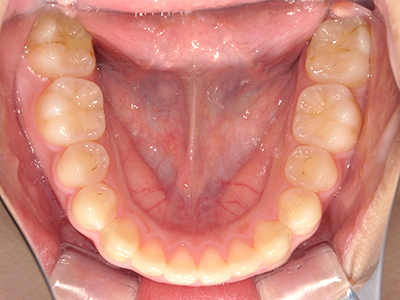

ないき歯科クリニックでは、これからあごが成長していくお子様や、歯並びが気になる成人の方など、さまざまな年代の方に対して矯正治療を行っています。

歯並びやかみ合わせを正しく整えると、笑顔や発音の自信につながり、むし歯・歯周病・口臭の予防にも役立ちます。

矯正装置を装着し、調整しながら少しずつ歯を移動させ、歯並びを整えていきます。